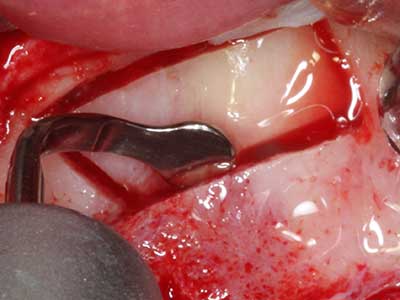

Sollen chirurgische Eingriffe mit unmittelbarer Knochenbeziehung an empfindlichen Strukturen wie Blutgefäßen oder Nerven erfolgen, so bergen rotierende Instrumente ein erhebliches Potential an iatrogener Schädigung. Gerade bei Nervdarstellungen nach iatrogener Schädigung, oder aber im Zuge einer Nervlateralisation für resektive und rekonstruktive Eingriffe oder Implantatinsertionen können piezoelektronische Geräte hilfreich sein Knochendeckel zu präparieren und nervnahe Hartgewebsanteile zu entfernen (Abb. 17-20). Ein leichter Kontakt des Nervstrangs zur Piezospitze bleibt dabei in der Regel folgenlos – allerdings kann eine unvorsichtige Vorgehensweise mit sägeartigen Bewegungen bzw. Ansätzen bei noch vorhandener knöcherner Unterlage durchaus temporäre oder aber auch permanente Nervschädigungen verursachen. Das Risiko einer solchen Schädigung wird jedoch als wesentliche geringer eingeschätzt als unter Anwendung von Säge- oder Fräsinstrumenten (Pereira, Gealh et al. 2014).

Indikation: Wurzelspitzenresektion

Wie bereits erwähnt lassen sich auch im Bereich der chirurgischen Zahnerhaltung Indikationsgebiete für die Piezochirurgie finden. Durch die Verwendung von speziellen Arbeitsspitzen wird die Darstellung der Wurzelspitze erleichtert, und gerade im unteren Prämolaren- und oberen Seitenzahnbereich lassen sich Nerven und Kieferhöhlenschleimhäute einfacher schützen. Bei undichtem apikalen Abschluss präparieren abgewinkelte Diamantspitzen zielgenau die Resektionskavität für das retrograde Wurzelfüllmaterial. Die Spitzen können durch die Ultraschalltechnik sehr grazil gestaltet sein, was Übersicht und Größe der Zugangskavität verbessert. So gehört in dieser Indikation die Anwendung der Ultraschallchirurgie zu den Standardverfahren der Wurzelspitzensresektion (Del Fabbro, Tsesis et al. 2010, Scarano, Artese et al. 2012).